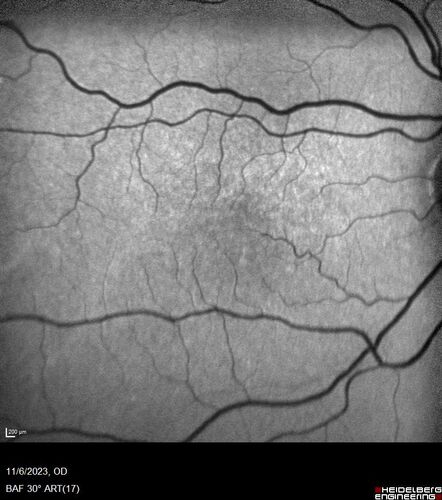

Albinism and Renal failure - Possible Hermansky-Pudlak Syndrome

65 year old female with foveal hypoplasia and renal failure since age 18. VA 20/40 OD, 20/63 OS